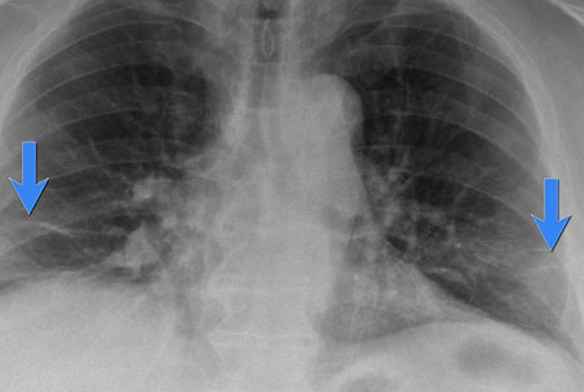

از کجا بفهمیم ریه آب آورده است؟ در ادامه علائمی در این خصوص را شرح میدهیم:

یکی از مهمترین علائم ادم ریوی در سالمندان، تنگی نفس است. این مشکل به ویژه هنگام دراز کشیدن بیشتر میشود و ممکن است باعث بیدار شدن شبانه سالمند به دلیل احساس خفگی و نیاز به نشستن شود. در برخی موارد، سالمندان ممکن است دچار خسخس یا سرفههای خشک و شدید شوند. این علائم نشاندهنده تلاش بدن برای به دست آوردن اکسیژن بیشتر و از بین بردن مایعات اضافی در ریههاست.

تورم در پاها و افزایش سریع وزن نیز از علائم دیگر ادم ریوی است. این تورم به دلیل تجمع مایعات در بدن ایجاد میشود و ممکن است به تدریج گسترش یابد. همچنین، سالمندان ممکن است خستگی شدیدی را تجربه کنند که ناشی از ناتوانی ریهها در تبادل اکسیژن و حذف مایعات اضافی است.